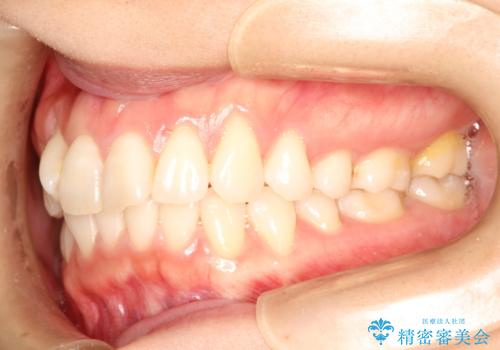

- 上の前歯のねじれを気にされて来院されました。

右上の前から2番目の歯が90度近くねじれて並んでいました。

こちらを当初セラミックでの治療をご希望でしたが、セラミック治療の限界と矯正治療のメリットをご説明をさせていただきました。

患者様に考えていただき、矯正治療で前歯をきれいにすることとしました。

インビザラインを使用して矯正することとしました。